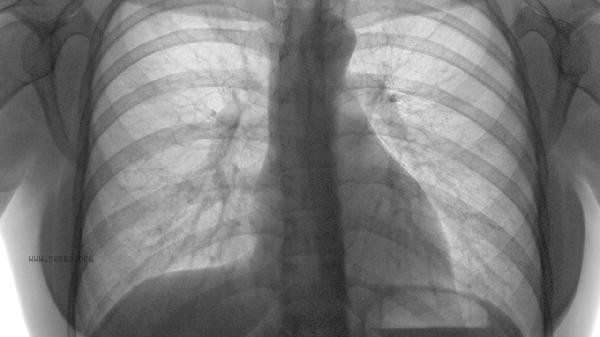

Once pulmonary embolism occurs, it usually means that the pulmonary artery is blocked by blood clots, which may cause breathing difficulties, chest pain, and even sudden death. The severity of pulmonary embolism mainly depends on the size of the thrombus, the site of obstruction, and the patient's basic health condition. Common causes include long-term bed rest, varicose veins, abnormal coagulation function, tumors, and cardiovascular disease.